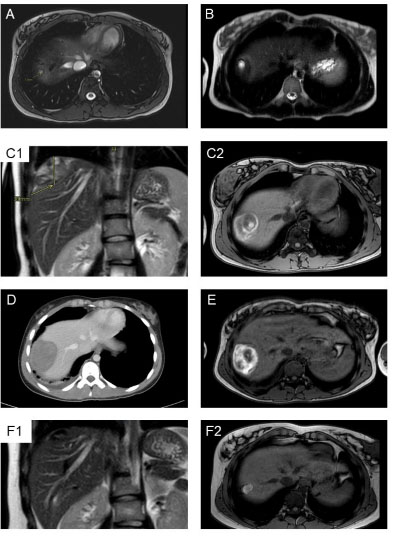

One month later the patient did a new TE that showed a mild to moderate pericardial effusion. Because of his previous disease he further did a cardiac CT that revealed a right ventricular (RV) pseudoaneurysm (Figure 2 and Figure 3), likely related to the previous pericardiocentesis.

Figure 2: Post-intravenous contrast cardiac CT. (A) Sagittal view and (B) Axial view: Right ventricular pseudoaneurysm (19×16 mm) with a narrow neck (4 mm) (white arrows), pericardial fat (blue arrowhead), and pericardial effusion (yellow stars).

Figure 3: 3D reconstruction cardiac CT: right ventricular pseudoaneurysm (white arrows).

Emergent pericardiocentesis was performed with clinical improvement. After this technique he developed an iatrogenic pseudoaneurysm, as it was confirmed by cardiac CT, which is corroborated by the literature.